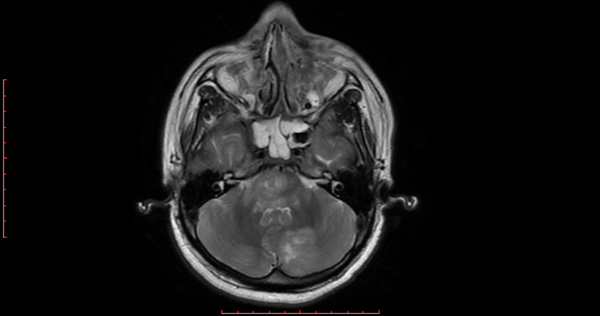

h.1) Resonancia magnética cerebral con corte sagital y secuencia T1 con gadolinio. Se encontró imagen heterogénea, con efecto de masa y zonas de reforzamiento en el interior. (Figura 1).

Figura 1. Resonancia magnética cerebral encorte sagital y secuencia T1 con gadolinio.